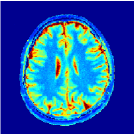

Two sets of experiments were conducted here: first, we used the 2D and 3D acquisition sequences for scanning a healthy volunteer’s brain (real-world acquisitions). Figures 6 and 7 display the parametric maps reconstructed from 2D spiral and radial readouts. We computed the T1, T2 and proton density (PD) maps using baseline reconstruction algorithms ZF, VS, LR, FLOR, AIR-MRF and our proposed LRTV. While baselines use DM either for quantitative inference or also during reconstruction (i.e. AIR-MRF), we further compare the DM-free LRTV’s performance when cascaded to DM, KM and MRFResnet for quantitative inference. For the 3D spiral acquisitions we compared LRTV and its closest competitor VS in Figure 8. Outcomes from other tested algorithm are displayed in the supplementary materials (Figure S5). Since FLOR does not use dimensionality-reduction, our system ran out of memory during 3D reconstruction; hence results are not reported in this case.

The LRTV-DM and LRTV-MRFResnet perform on par, and both outperform all tested baselines for reconstructing T1, T2 and PD maps in all acquisition schemes. This can be observed both visually in Figures 6, 7, 8, S2 and S3, and quantitatively in Table IV across all tested metrics. Other baselines were unable to successfully remove the under-sampling artefacts in TSMIs, and these errors propagated to the parameter inference phase and resulted in inaccurate maps. Temporal-only priors incorporated within LR are shown insufficient to regularise the inverse problem and LR sometimes (e.g. 2D spiral acquisitions) can admit solutions with even stronger artefacts than the model-free ZF baseline. This issue was previously studied for other non-Cartesian MRF readouts that similar to our spiral/radial trajectories, miss to sample the corners of the k-space in all timeframes (see section 2.2.2 and figure 2 in [19]). In the absence of reference for the k-space corners information, the LR iterations despite minimising the objective can converge to solutions with high-frequency artefacts, as visible in the computed maps. This highlights the need for adding an appropriate spatial-domain regularisation. FLOR reduces the LR’s artefacts but this improvement is limited because the suggested nuclear norm penalty does not incorporate an explicit spatial regularisation. Further for reducing artefacts, FLOR can introduce an undesirable bias in the computed T1/T2 maps e.g. see error maps in Figures S2 and S3. The non model-based VS baseline incorporates spatial regularisation and results in spatially smoother maps than ZF and LR, but it is unable to output artefact-free images. Further and consistent with our in-vitro experiment, we observe that VS overestimates the T2 values (e.g. in White and Grey matter regions) in tested 2D acquisitions i.e. the spatial regularisation trades off agains the quantification accuracy. The model-based AIR-MRF adds spatial regularisation through 2D/3D low-pass Gaussian filters however this trades off the sharpness of the computed maps and can increase the errors at the tissue boundaries (we searched Gaussian spreads that keep the blurs and high-frequency artefacts minimal). For our acquisition readouts, Gaussian filters performed better than disk filters of [19] for avoiding strong Gibbs artefacts. On the other hand, the spatiotemporally regularised LRTV greatly improves the TSMI reconstructions i.e. 4 dB enhancement compared to the closest competitor baseline (Table IV). This enables computing accurate and aliased-free multi-parametric inference using DM or the DM-free learning-based alternative MRFResnet as visible in Figures 6, 7, 8, S2 and S3. MRResnet and DM score competitive quantitative inference results i.e. T1 and T2 MAPE less than 5% and 9%, respectively (Table IV). KM also outputs comparably accurate T1 maps, however this shallow learning model despite having a model size larger than MRFResnet, is unable to learn accurate T2/PD quantification and it results in poor estimated maps, consistent with our observations in section VI-C.